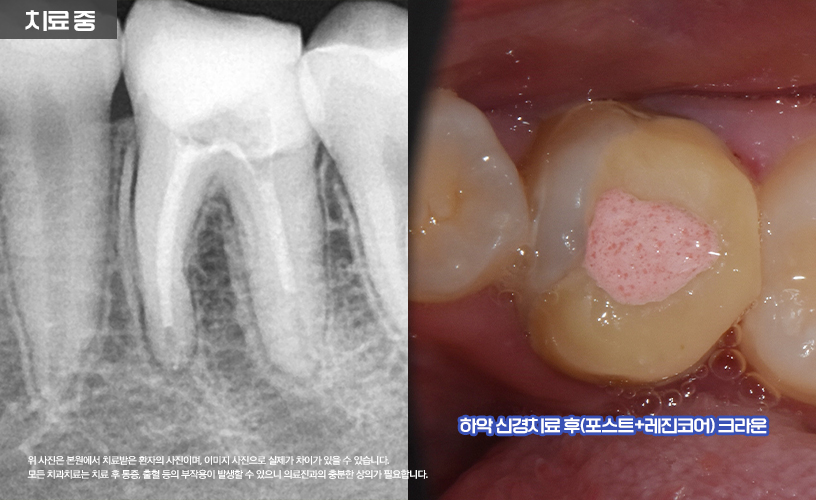

나머지 상, 하악 16,26,36,46번 치아는

신경치료를 통해 치료가 진행됩니다.

먼저 충치로 인해 파절의 정도가 심한 상태이기

때문에 신경치료와 함께 포스트+레진 코어를 통해

얼마 남지 않은 치아의 기둥을 세워

튼튼하게 잡아주었습니다.